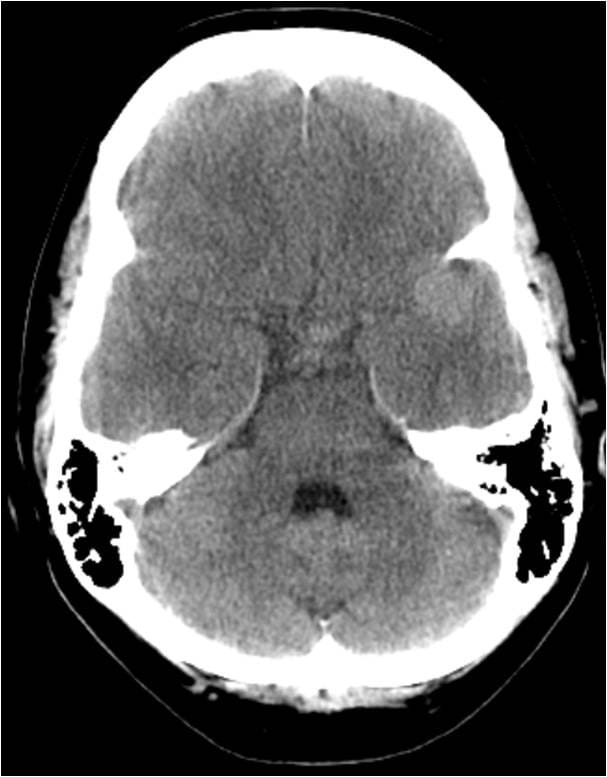

This video documents the surgical clipping of a giant middle cerebral artery aneurysm. The patient is a 56-year-old woman with a Grade I subarachnoid hemorrhage.